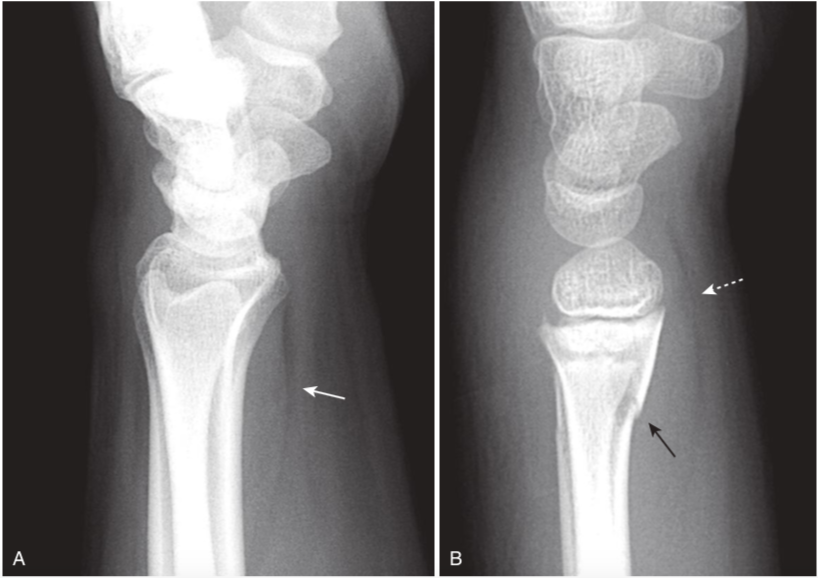

Normal and abnormal pronator quadratus fat plane.

Soft tissue abnormalities can provide clues to the presence of subtle fractures or help confirm the significance of a questionable finding. A,Here is an example of a normal fascial plane produced by the pronator quadratus (white arrow points to lucency)on the volar aspect of the wrist, compared with the bulging fascial plane (dotted white arrow)in (B),which has occurred because of soft tissue swelling accompanying a fracture of the distal radius (black arrow).